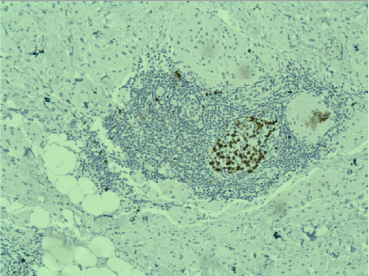

A frozen section was performed during surgery and the result was “invasive tumor, suspicious for malignancy”. Radical left mastectomy was performed with axillary lymph nodes dissection. The histological examination of the symptomatic lesion (11 mm) revealed a tumor, composed of nests of epitheloid tumor cells with monomorphous nuclei with occasional nucleoli, areas with spindle tumor cells in a fibrous background with hyaline change, areas with mature adipocytes. Peripheral nerves were surrounded by tumor nests (Figure 1). Scattered lymphocytic infiltrates were also found. PAS reaction revealed single positive granules in a few tumor cells (Figure 2). The described histological findings are observed in both mammary MFB and granular cell myoblastoma. Immunohistochemical analysis was performed. The tumor cells were positive for: S-100 protein (Figure 3), CD68 (Figure 4), Vimentin (Figure 5). The proliferative index detected with Ki67 is low (1-2%) (Figure 6). The tumor cells were negative for ER, PR and HER. The histological examination of the dissected lymph nodes revealed sinus histiocytosis, follicular hyperplasia and lipomatosis. Metastases were not found.

Figure 1. Peripheral nerves surrounded by nests of tumor cells, Н&E, x10